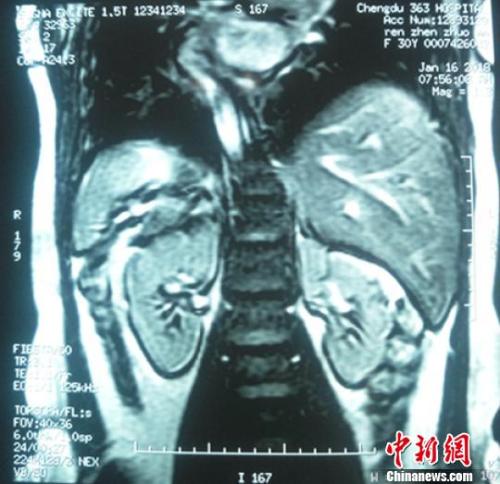

镜面人核磁共振检查画面,内脏位置与常人相反?!⊥跖?摄

据介绍,“镜面人”即心脏、肝脏、脾脏、胆等器官的位置与正常人相反,心脏、脾脏在右边,肝脏位于左边,心、肝、脾的位置好像是正常脏器的镜面像,其发生几率为百万分之一。